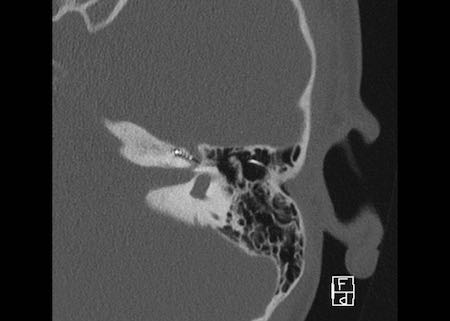

Bên trái là hình ảnh của một bé gái 2 tuổi.

Các hình ảnh từ kết quả chụp CT được thực hiện trước khi cấy ốc tai điện tử.

Quan sát thấy dị dạng nhẹ ở đỉnh ốc tai – không có sự phân tách giữa vòng thứ hai và vòng thứ ba, và trụ ốc tai xương vắng mặt.

Cống tiền đình bình thường.